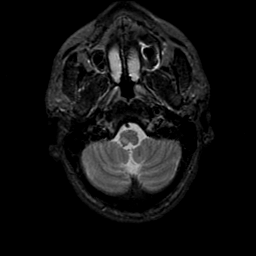

MR Study #9, April 14, 1991 -- Slice #6